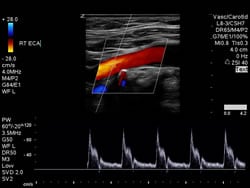

Carotid artery disease may also be picked up when having other tests or scans in the neck area. There are several types of scan for carotid artery disease. The most common is an ultrasound (sometimes called a carotid doppler). This is a simple and painless procedure where a probe is passed over the carotid arteries to scan and make pictures of them. It can then be determined if there is any narrowing present. This is the easiest thing to do but you can also do scans using computerised tomography (CT) or magnetic resonance imaging (MRI). All of these scans are good at detecting carotid artery disease.